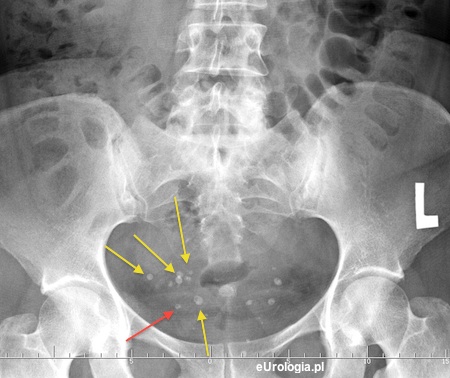

Mam kolkę nerkową od kilku dni i rodzę kamień, który jest w ujściu moczowodu prawego - wniosek z badania USG jamy brzusznej z pełnym pęcherzem moczowym. Na wykonanym zjęciu RTG jamy brzusznej radiolog opisał liczne flebolity w miednicy małej. Na zdjęciu rzeczywiści widać liczne białe cienie. Jak urolog odróżni złóg w moczowodzie od flebolitu?